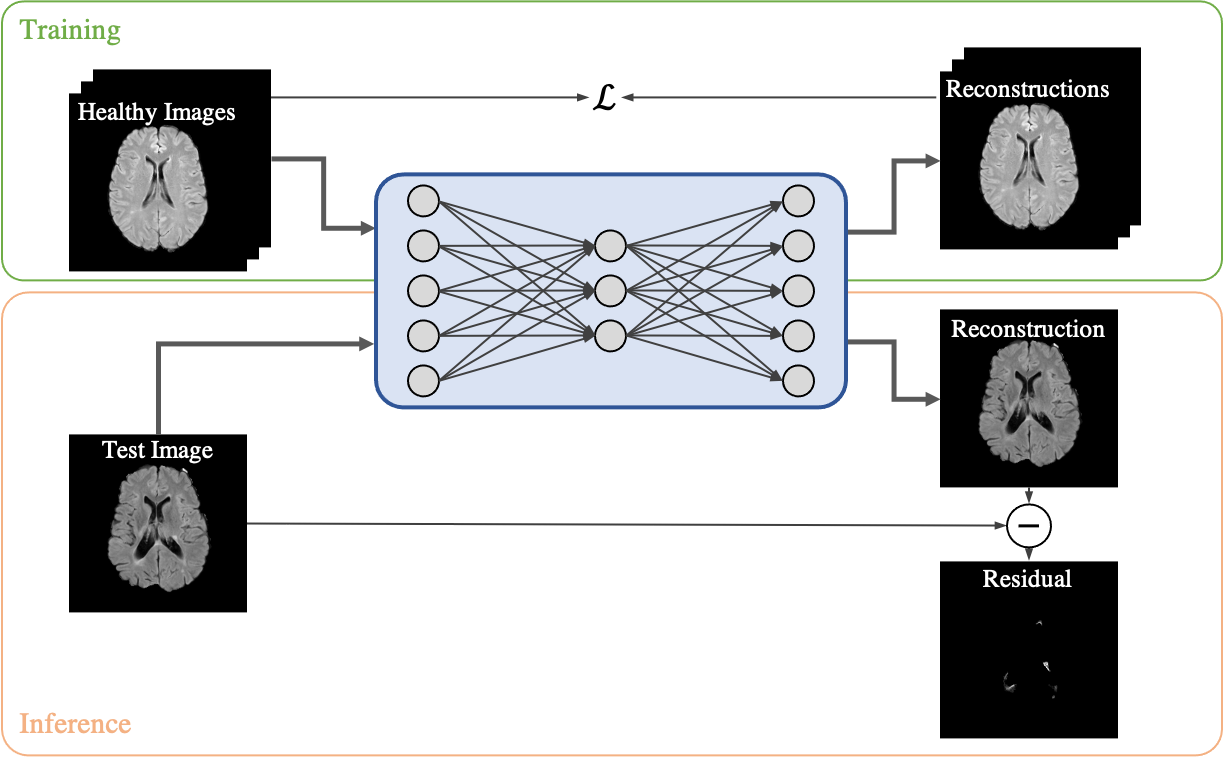

Several methods for SAS in brain images have been introduced in recent years. Most of them are based on semi-supervised training of Autoencoders. The principle is depicted in Figure 1. The model is trained on images without anomalies only to learn a distribution of healthy brain images. During inference, the newly presented image is processed by the model to obtain a \sayhealthy version of the same image. Usually, an anomaly map is then obtained by computing the residual between the input image and its \sayhealthy version. Pixels of the anomaly map above a threshold are then considered anomalous.

Recently, SAS achieved impressive successes in automatic industrial defect detection [9, 17, 13, 25] on the MVTec-AD data set [8]. In the medical imaging domain, most works have focused on the detection of pathologies in brain images. Here, mostly autoencoder-based approaches have been applied so far [1, 26, 5, 27, 12, 11, 4]. These techniques use only images from healthy subjects as training data to learn the distribution of \saynormal brain anatomies. During inference, most of the approaches compute a so-called anomaly map as the pixel-wise residual between the input image and a predicted \saynormal version of the same image generated by the model, that is closer to the training distribution. Common anomaly types in brain MRI are tumors and lesions from specific diseases such as multiple sclerosis (MS). In fact, all of the aforementioned works evaluate their performance by detecting either of them or both. In clinical routine, MR images are typically acquired using different sequences or weightings in which the tissues appear in specific intensities. Among the most common ones are T1, T2, Fluid-attenuated inversion recovery (FLAIR), or Proton density (PD)-weighting. In FLAIR images – a standard protocol for routine clinical imaging in neurology – lesions are hyperintense compared to the rest of the tissue and also tumors are usually brighter. Because of this, FLAIR images are often used in SAS of brain MRI [1, 5, 4, 20].